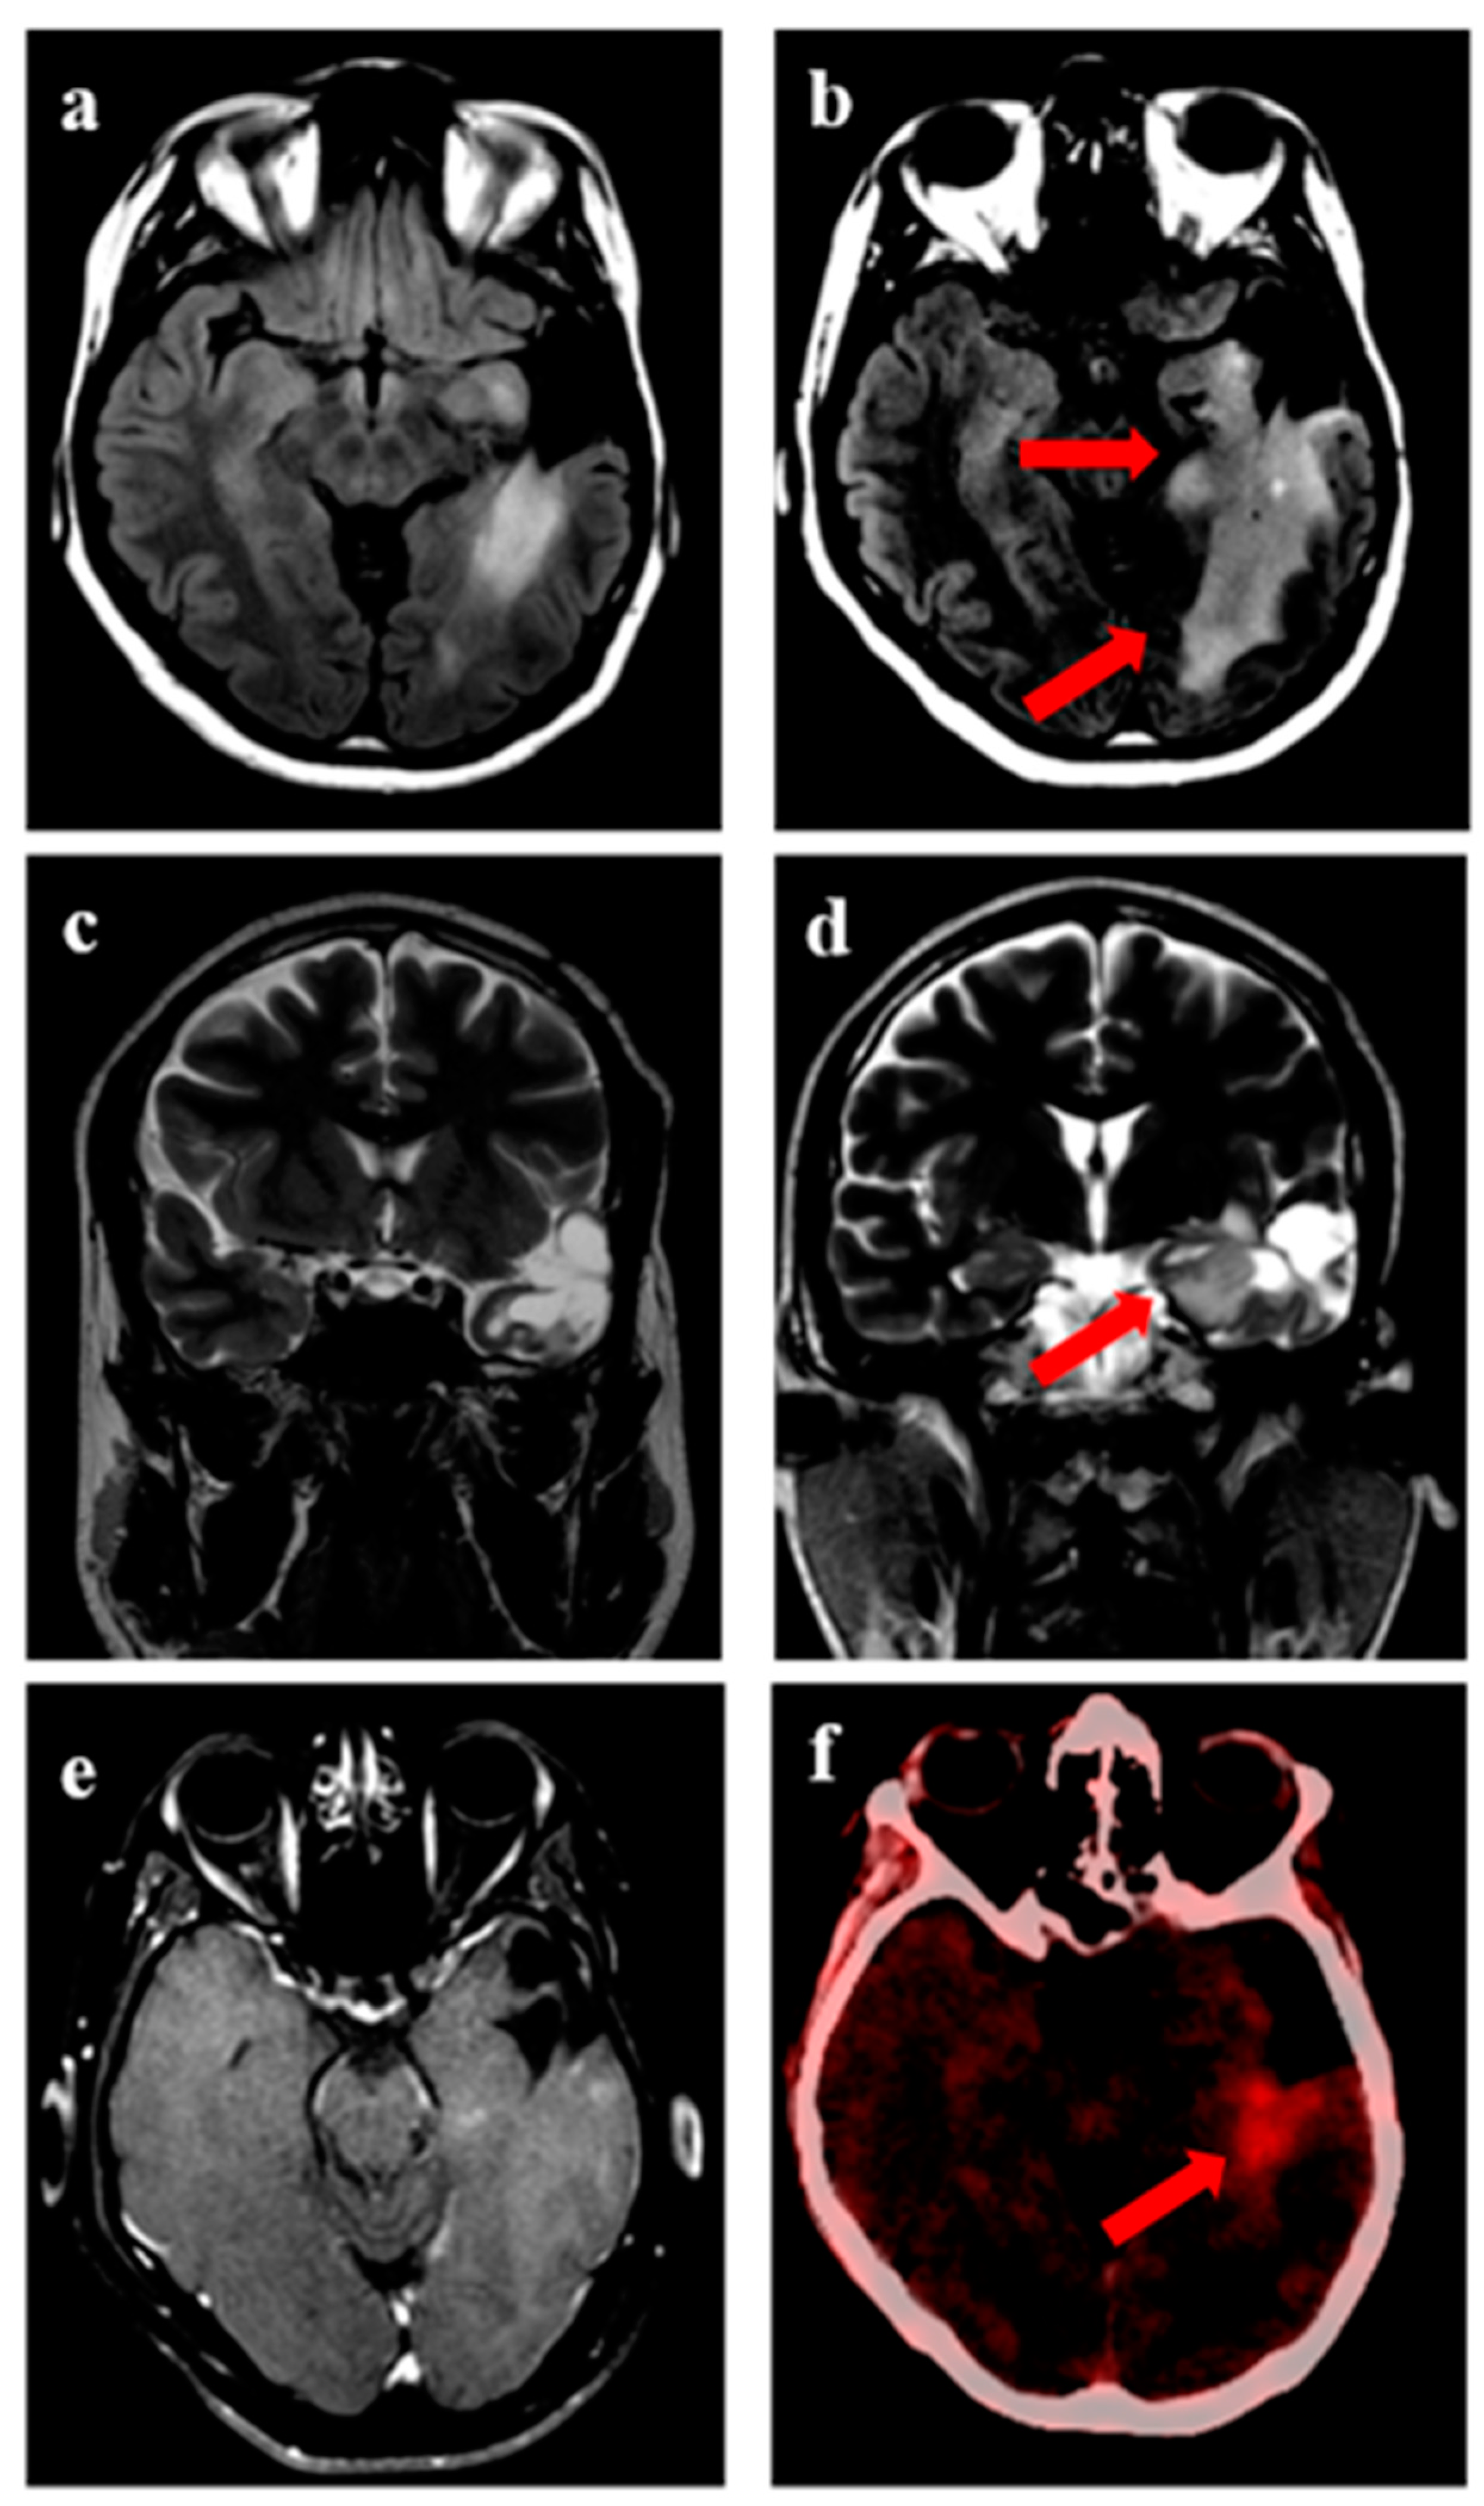

| Imaging modality during recurrence | |

| MRI alone | 27 (73%) |

| PET alone | 3 (8%) |

| MRI and PET | 7 (19%) |